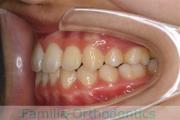

かみ合わせを治して食事の不便を無くしたい、とのことで来院されました。相当に強い上顎前突(前歯の突出)を認めるため、上下左右から小臼歯を抜歯してマルチブラケット法にて治療を行いました。ほぼ2年、25回程度の通院が必要でした。前歯の移動量が大きく、歯根吸収のリスクが高いケースでした。